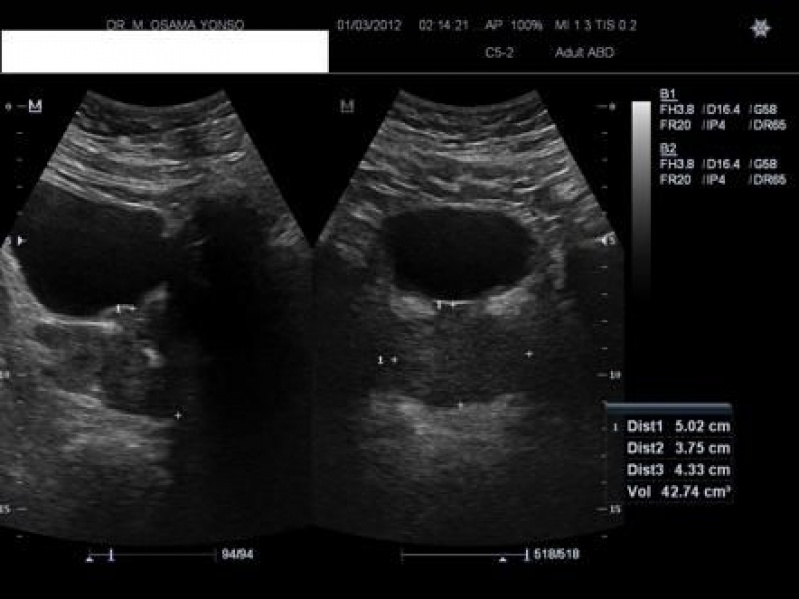

Ultrassonografias de Próstatas

O ultrassom é um exame de imagem usado para obter informações precisas sobre tamanho e interface da estrutura interna de tecidos e órgãos do corpo humano. Com os exames de ultrassonografias de próstatas, o médico pode identificar a presença de tumores da próstata, tamanho elevado do órgão e obter outras informações. É importante destacar que o ultrassom não substitui o exame de toque retal, trata-se de um exame complementar.

O ultrassom via transretal é feito com a introdução de um transdutor endocavitário para visualização da estrutura da próstata, tornando-se um exame fundamental para complementar o diagnóstico médico. Com o exame, o médico pode proceder corretamente para determinar qual tratamento é mais apropriado para o paciente.

A ultrassonografia da próstata via transretal é essencial para um diagnóstico preciso de câncer de próstata. Além de coleta de imagens da estrutura do órgão, a introdução de transdutor endocavitário permite a coleta de material para análise de biópsia em laboratório, confirmando as suspeitas do médico. Após o exame, o urologista pode orientar que o paciente faça a cirurgia de próstata.